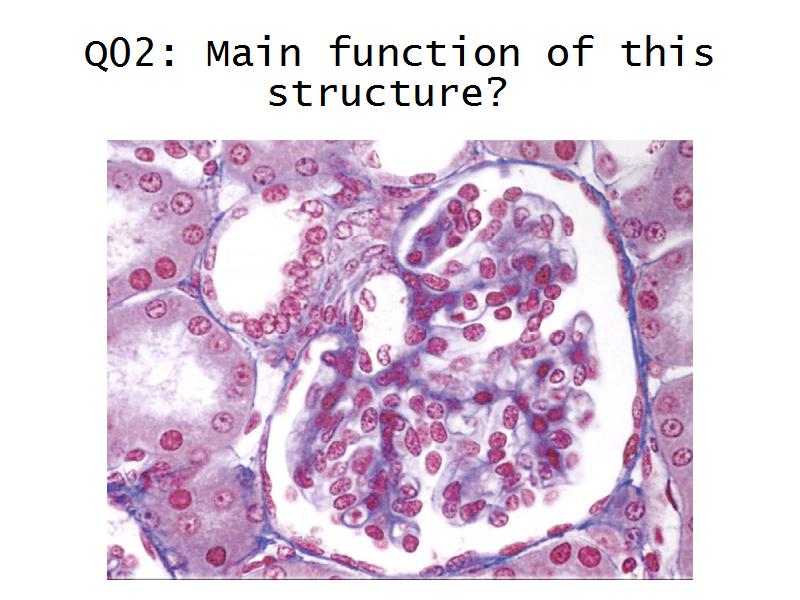

Kidney

Kidney

Slides 28 & 76

Kidney: Objectives

- Basic anatomy of the kidney

- Basic arrangement of nephrons and collecting tubules in the kidney

- Structure of the nephron and collecting tubules

- The renal corpuscle

Kidney: Tasks

- Make an annotated drawing of the macroscopic view of the kidney.

- Make an annotated diagram of a nephron, including the juxtaglomerular apparatus. Indicate the flow of blood and water in each part, and how solutes are filtered, secreted and reabsorbed.

- Complete the drawings for each slide in the practical workbook.